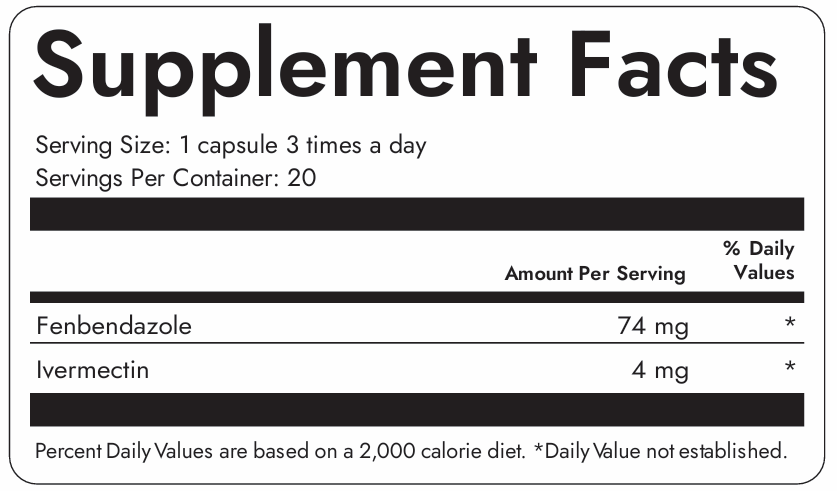

Take 1 capsule 3 times daily with meals. For best results, maintain consistent timing and follow the recommended dosage. Consult with your healthcare provider before starting any new supplement regimen.

Clinically trusted for decades, Ivermectin helps bind and flush out parasites, biofilm waste, and immune disruptors hiding deep in tissues. Our formula uses only the purest medical-grade Ivermectin—no fillers, no toxins.

Fenbendazole is a well-researched anti-parasitic compound known for its powerful detox and cellular repair support. Backed by emerging science, it’s used for everything from gut resilience to systemic cleanup.

Crafted with premium and lab-tested Ivermectin and Fenbendazole to help your body flush out unwanted toxins and support optimal gut and immune health.